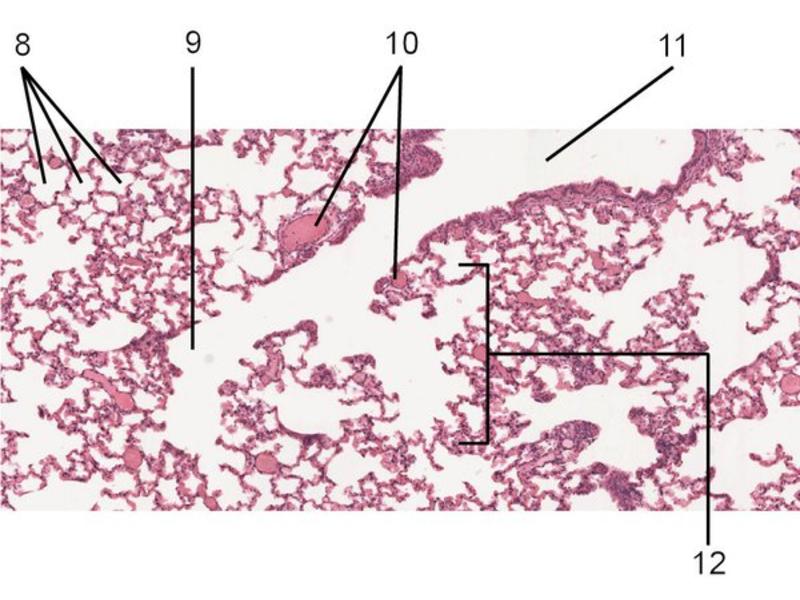

Slides: Respiratory System

- Slide 72 & 74: Lung

Lungs